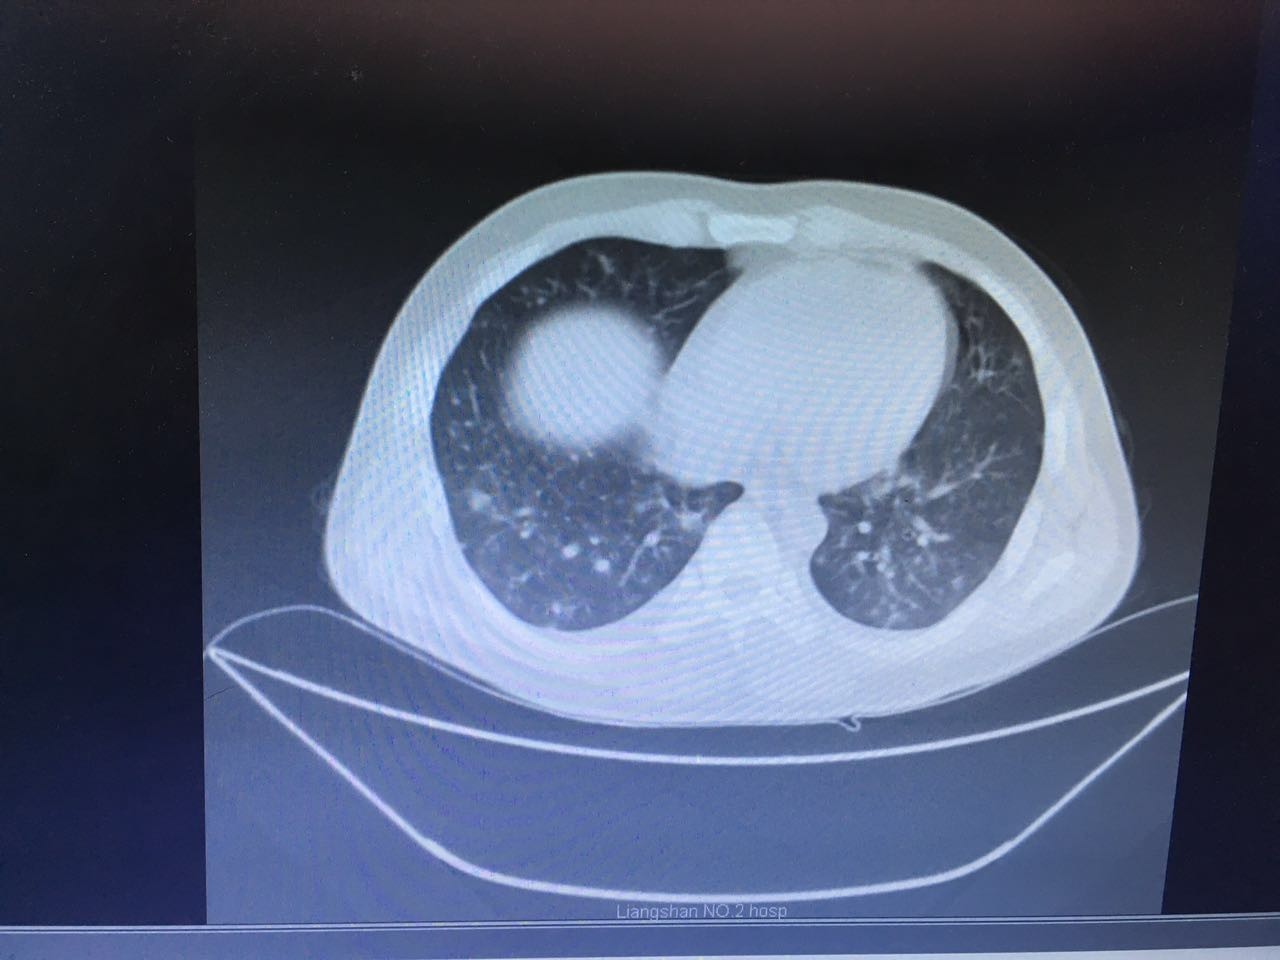

最后患者在治疗的过程中,联系了两位曾经和他在小河里摸鱼的朋友,居然都在高热。一个因为病情较重,已经转往省级医疗机构……治疗经过不详。还有一个因为肺部感染就住在我院呼吸科,我们后来接手了呼吸科的患者,也给 他完善了肠镜检查,获得了同样的结论。两人的肺部病灶及肠镜表现虽然轻重不同,但是基本上是类似的。(图片6-10)

图6

图7

图8

图9

图10